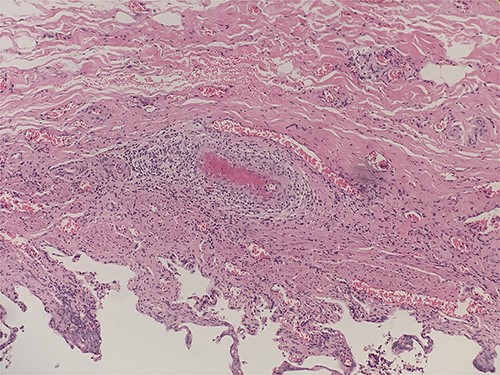

Intraluminal thrombi, fibrinoid necrosis with perivascular infiltration by lymphocytes, neutrophils, and eosinophils (H&E 200X).